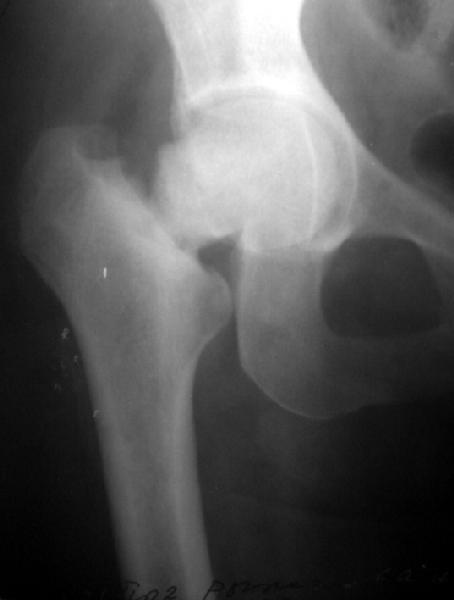

Женщина лет 40 переведена к нам из городской больницы с переломом шейки бедра.

Упала дома 5.11.02. С ее слов, в послдений год лечилась консервативно от якобы коксартроза с этой же стороны. Снимков не делали. Этот сустав болит последние несколько месяцев. На снимках обращает на себя "замыленность" краев. Не усталостный ли это перелом? Дама полноватая. Ограничения амплитуды движений до травмы она не отмечала.Мнения о тактике у нас разошлись в диапазоне от остеосинтеза винтами до эндопротезирования, с остеотомиями между ними. Помогите, пожалуйста, обосновать выбор.

Мне кажется с этой женщиной надо прежде всего хорошо поговорить. Перелом выглядит несвежим (не менее 4-6 месяцев) и не патологическим. Усталостный ведь тоже патологический! По-моему, был у неё импактный относительно устойчивый перелом шейки, образовавший фиброзный N-Union. Поэтому были у неё боли и "коксартроз". При последнем падении она его дез-импактировала.

To my eye, it does have a sclerotic edge to it, but it may just be projection. Does she have diabetes or other metabolic- eg renal problems? Jim Carr

Derek Cooke 23 Ноябрь 2002, 20:35

The very clear ends and sclerosis suggest an osteitis. Difficult to tell re the hip but there appears to be sclerosis here in the acetabulum too. I would be very suspicious of Pagets. Does she have any metabolic bone

abnormalities, raised Alk Phos?. I think no place for hip fixation here as this is a pathological #, but a THR. May be difficult because of the sclerosis and hypervascular.

To me the whole head, neck and adjacent acetabular area look sclerotic.

Do you have x-ray of the whole pelvis with both hips for comparison of areas. Also like James carr suggested a metabolic work up.

This one was made at the initial hospital two days before transfer.

Прилагаю еще одну рентгенограмму - обзорный снимок таза от 11 ноября, еще до перевода к нам. Ранее были посланы снимки, сделанные 13 ноября

уже у нас.

Думаю прежний снимок мало что меняет. Есть базо-цервикальный перелом, на мой взгляд, несвежий. Снимок 11.11.02 технически хуже 13.11.02 и сделан в несколько иной проекции. Жаль что в обеих случаях нет аксиального снимка шейки, на мой взгляд просто необходимого для диагноза.